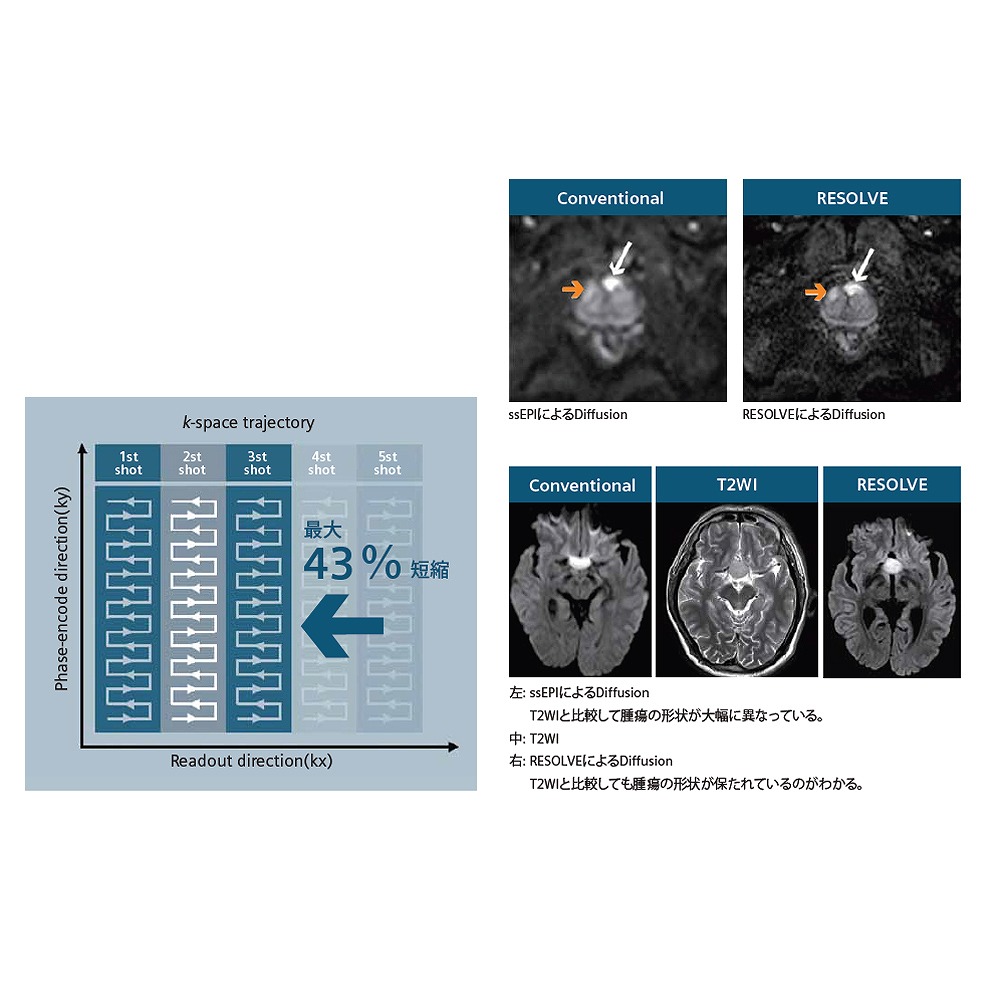

●高密度コイルTim4Gと最新ソフトウェアバージョンE11によるさまざまな臨床へのアプローチで、高精細画像や臨床有用性の高い画像の描出を可能にします。